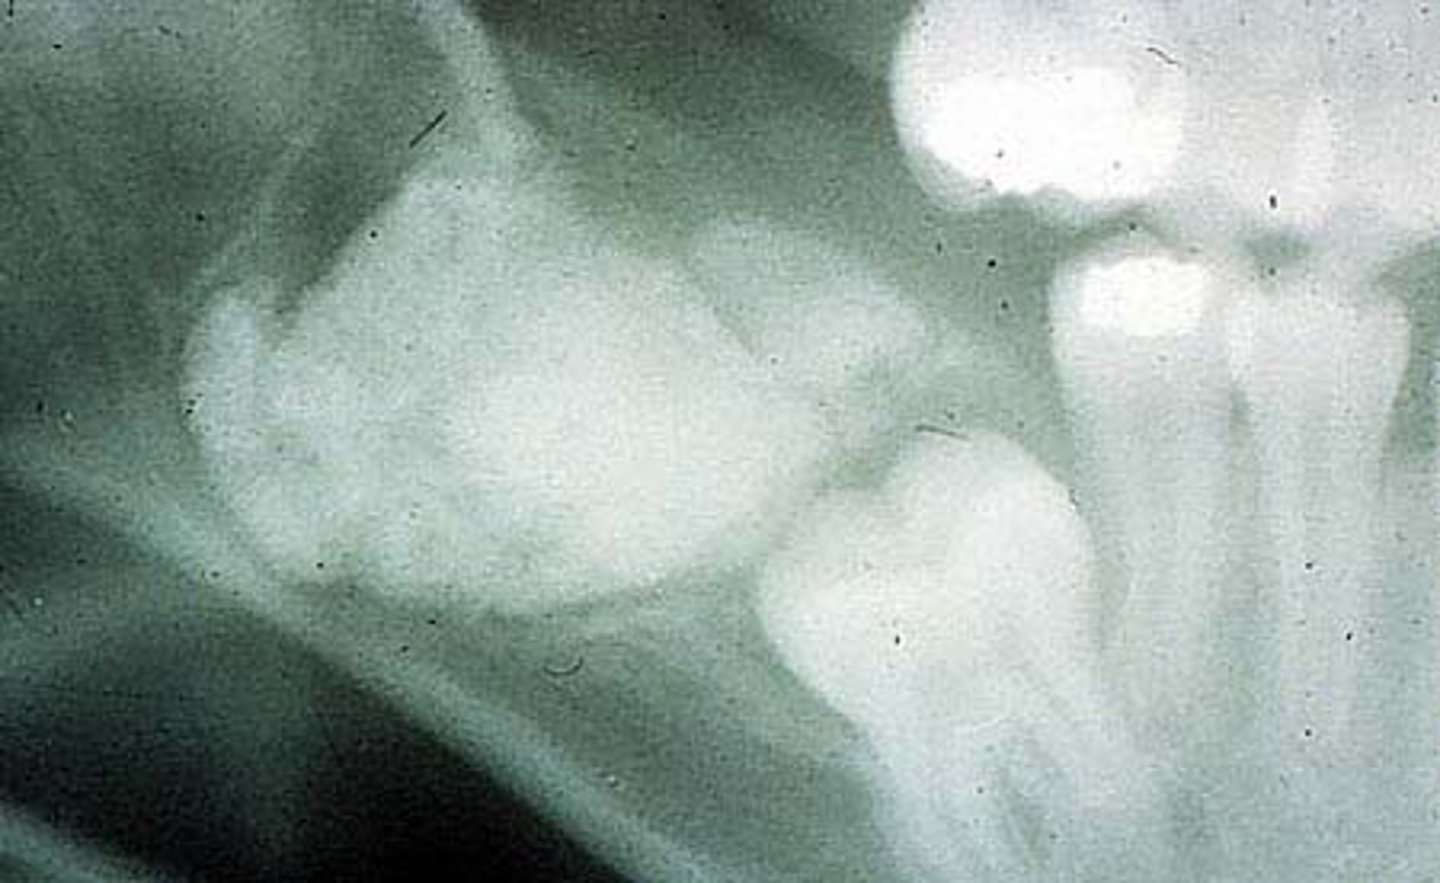

Complex odontoma is an

odontogenic tissues but NOT having small tooth appearing structures

Complex odontoma radiographic

radiopaque mass

Complex odontoma